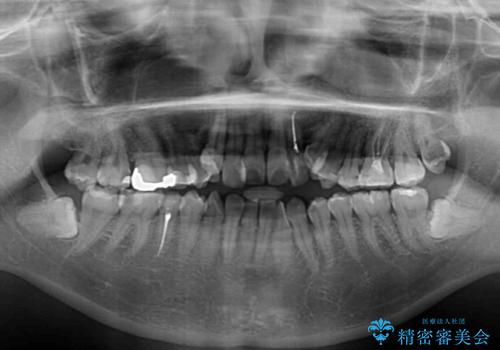

- 上下の歯が非接触であり、八重歯やむし歯を気にして来院された患者様です。

下顎骨の左右偏位はあるものの、上顎骨幅が相対的に狭い状態であったので、奥歯の咬み合わせが非常に乱れていました。

急速拡大装置により上顎骨幅を側方に拡大し、それを利用して八重歯を歯列に納めることにしました。

矯正治療後は全顎的にむし歯が多いため、セラミッククラウンやインレーにより補綴治療を行うこととしました。